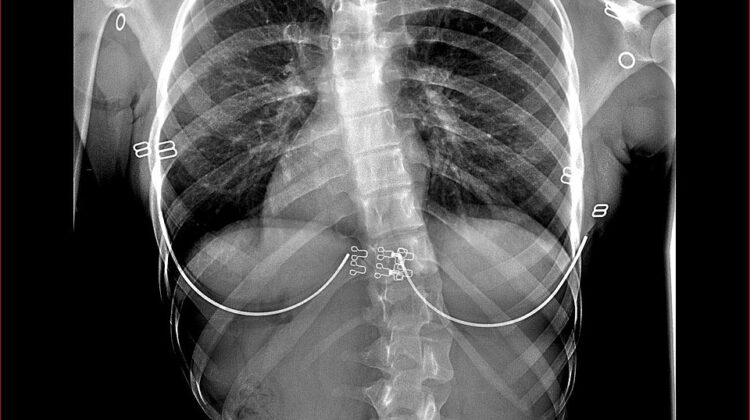

يعاني بعض المراهقين من اعوجاج العمود الفقري المراهقي مجهول السبب (Adolescent Idiopathic Scoliosis – AIS)، وهو أكثر التشوهات الشائعة للعمود الفقري في هذه المرحلة العمرية. تتراوح شدته من اعوجاج بسيط لا يسبب أعراضًا، إلى حالات متقدمة قد تؤثر على المظهر العام والصحة الجسدية والنفسية.

مع تقدم البحوث، لاحظ الأطباء أن التغيرات في صورة الجسم لدى الفتيات المصابات باعوجاج العمود الفقري يمكن أن تشبه بعض السمات المرتبطة باضطرابات الأكل (Eating Disorders – EDs)، مثل الانزعاج من شكل الجسم أو القلق المفرط بشأن الوزن. هذه الملاحظات دفعت الباحثين لاستكشاف العلاقة بين اعوجاج العمود الفقري واضطرابات الأكل والجودة الحياتية لدى المراهقات.